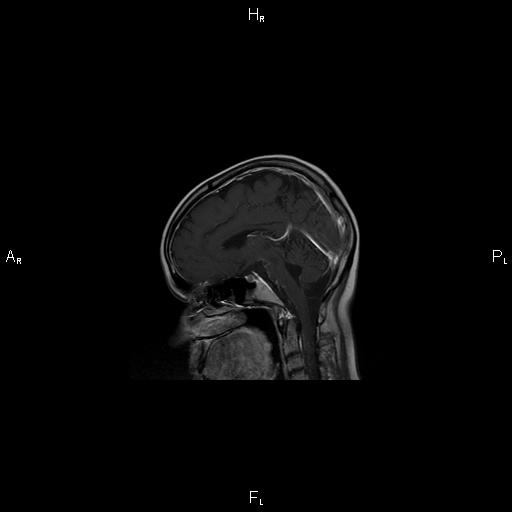

11. Рис. 4

Тема

Тип Материалы исследования

Метаданные ▾